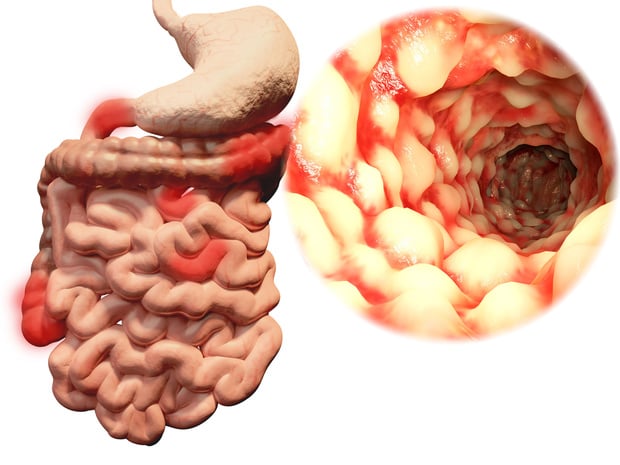

Maladie de crohn : modèle de risque pour les parents de premier degré

13/01/2025

Malgré les avancées thérapeutiques pour la maladie de crohn, environ la moitié des patients développent des complications nécessitant une intervention chirurgicale. une détection précoce de la maladie est cruciale pour améliorer les résultats pour les patients. le groupe de recherche canadien ccc-gem a mis au point un score de risque pour les personnes présentant une susceptibilité familiale pour cette maladie inflammatoire de l'intestin.